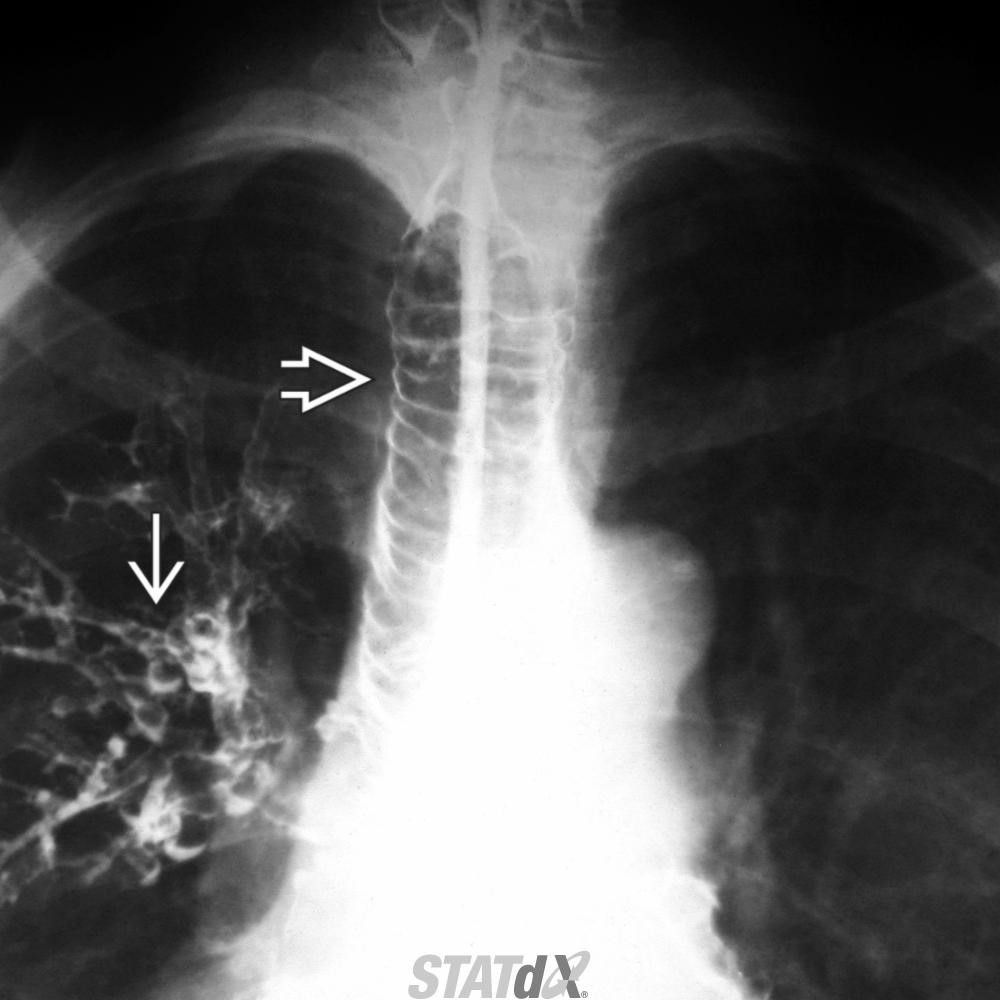

Tracheobronchomegaly (Mounier-Kuhn syndrome)

Dilatation of trachea & central bronchi that impairs ability to clear mucus

Atrophy or absence of elastic fibers & thinning of smooth muscle layer in trachea & main bronchi

Tracheobronchomegaly; Mounier-Kuhn syndrome

Coronal CECT of a patient with tracheobronchomegaly shows marked dilatation of the trachea (open arrow) and mainstem bronchi . The large airways have a corrugated appearance. Right lower lobe pneumonia (straight arrow) and paraseptal emphysema are also present.